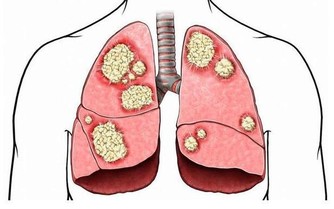

四、咳嗽怎麼喝:

多喝熱水,遇到咳嗽、有痰這樣的症狀,很多人都感到憋氣、難受,痰液難於咳出。這時候有什麼好的辦法來緩解呢?就是要多水,而且還要多喝熱水。首先,熱水可以起到稀釋痰液,使痰易於咳出的作用;其次,飲水的增多增加了尿量,可以促進有害物質的迅速排泄;另外呢,還可以撫慰氣管與支氣管黏膜的充血和水腫,使咳嗽的頻率降低。這樣的話,人就會感到舒服通暢很多。